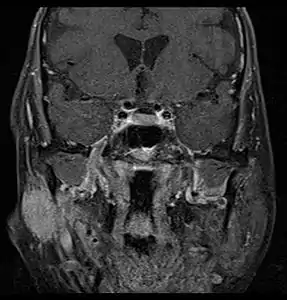

Coronal MRI showing right parotid adenoid cystic carcinoma with perineural spread of tumor: The tumor originates in the right parotid gland and spreads along the trigeminal nerve via the auricuotemporal branch extending intracranially through the foramen ovale at the skull base towards Meckel's cave.

Coronal MRI showing right parotid adenoid cystic carcinoma with perineural spread of tumor along the facial nerve extending to the stylomastoid foramen